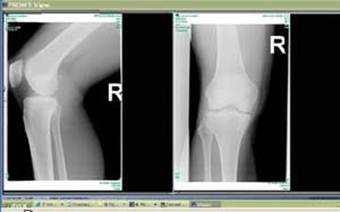

Сравнение рентгеновского снимка и МР томограммы коленного сустава.

| Рентгеновский снимок | МР томограмма |